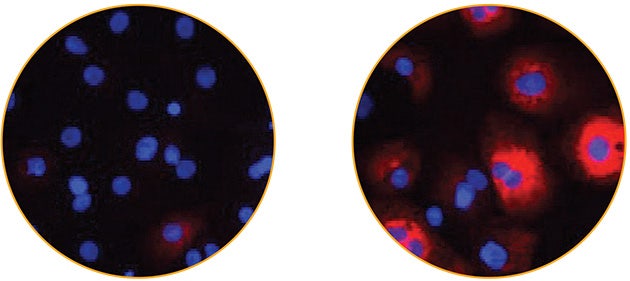

Increased levels of BNP is one of many proteins whose expression is altered during cardiac hypertrophy. Here, the expression of BNP was determined using high-content imaging by labeling BNP with a fluorescent antibody to measure cytoplasmic BNP staining (Figure 2A). In this experiment, iCell Cardiomyocytes were treated with a 10-point dilution series of ET- 1. A dose response curve was generated for the ET-1 induced expression of BNP in cardiomyocytes by plotting the BNP signal per cell against the log concentration of compound treatment (Figure 2B). The curve was then fit to generate an EC50 value from the ET-1 dose-response.

Figure 2A. BNP expression in iCell Cardiomyocytes before and after ET-1 addition. Images of iCell Cardiomyocytes untreated (left) or stimulated with 10 nM ET-1 for 18 hours (right). Cells were labeled with antibodies to detect BNP expression (red), and nuclei were stained with Hoechst 33342 (blue). Images acquired at 20x magnification. The area of BNP signal was used to calculate the levels of BNP expression1.